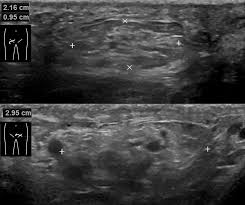

신장 및 요로계 질환

- 신장결석: 콩팥 내 결석 확인 가능

- 수신증: 요관 폐쇄 등으로 신장이 부어 있는 상태 확인

- 신장 종양, 낭종: 악성·양성 종양 여부 1차 판별